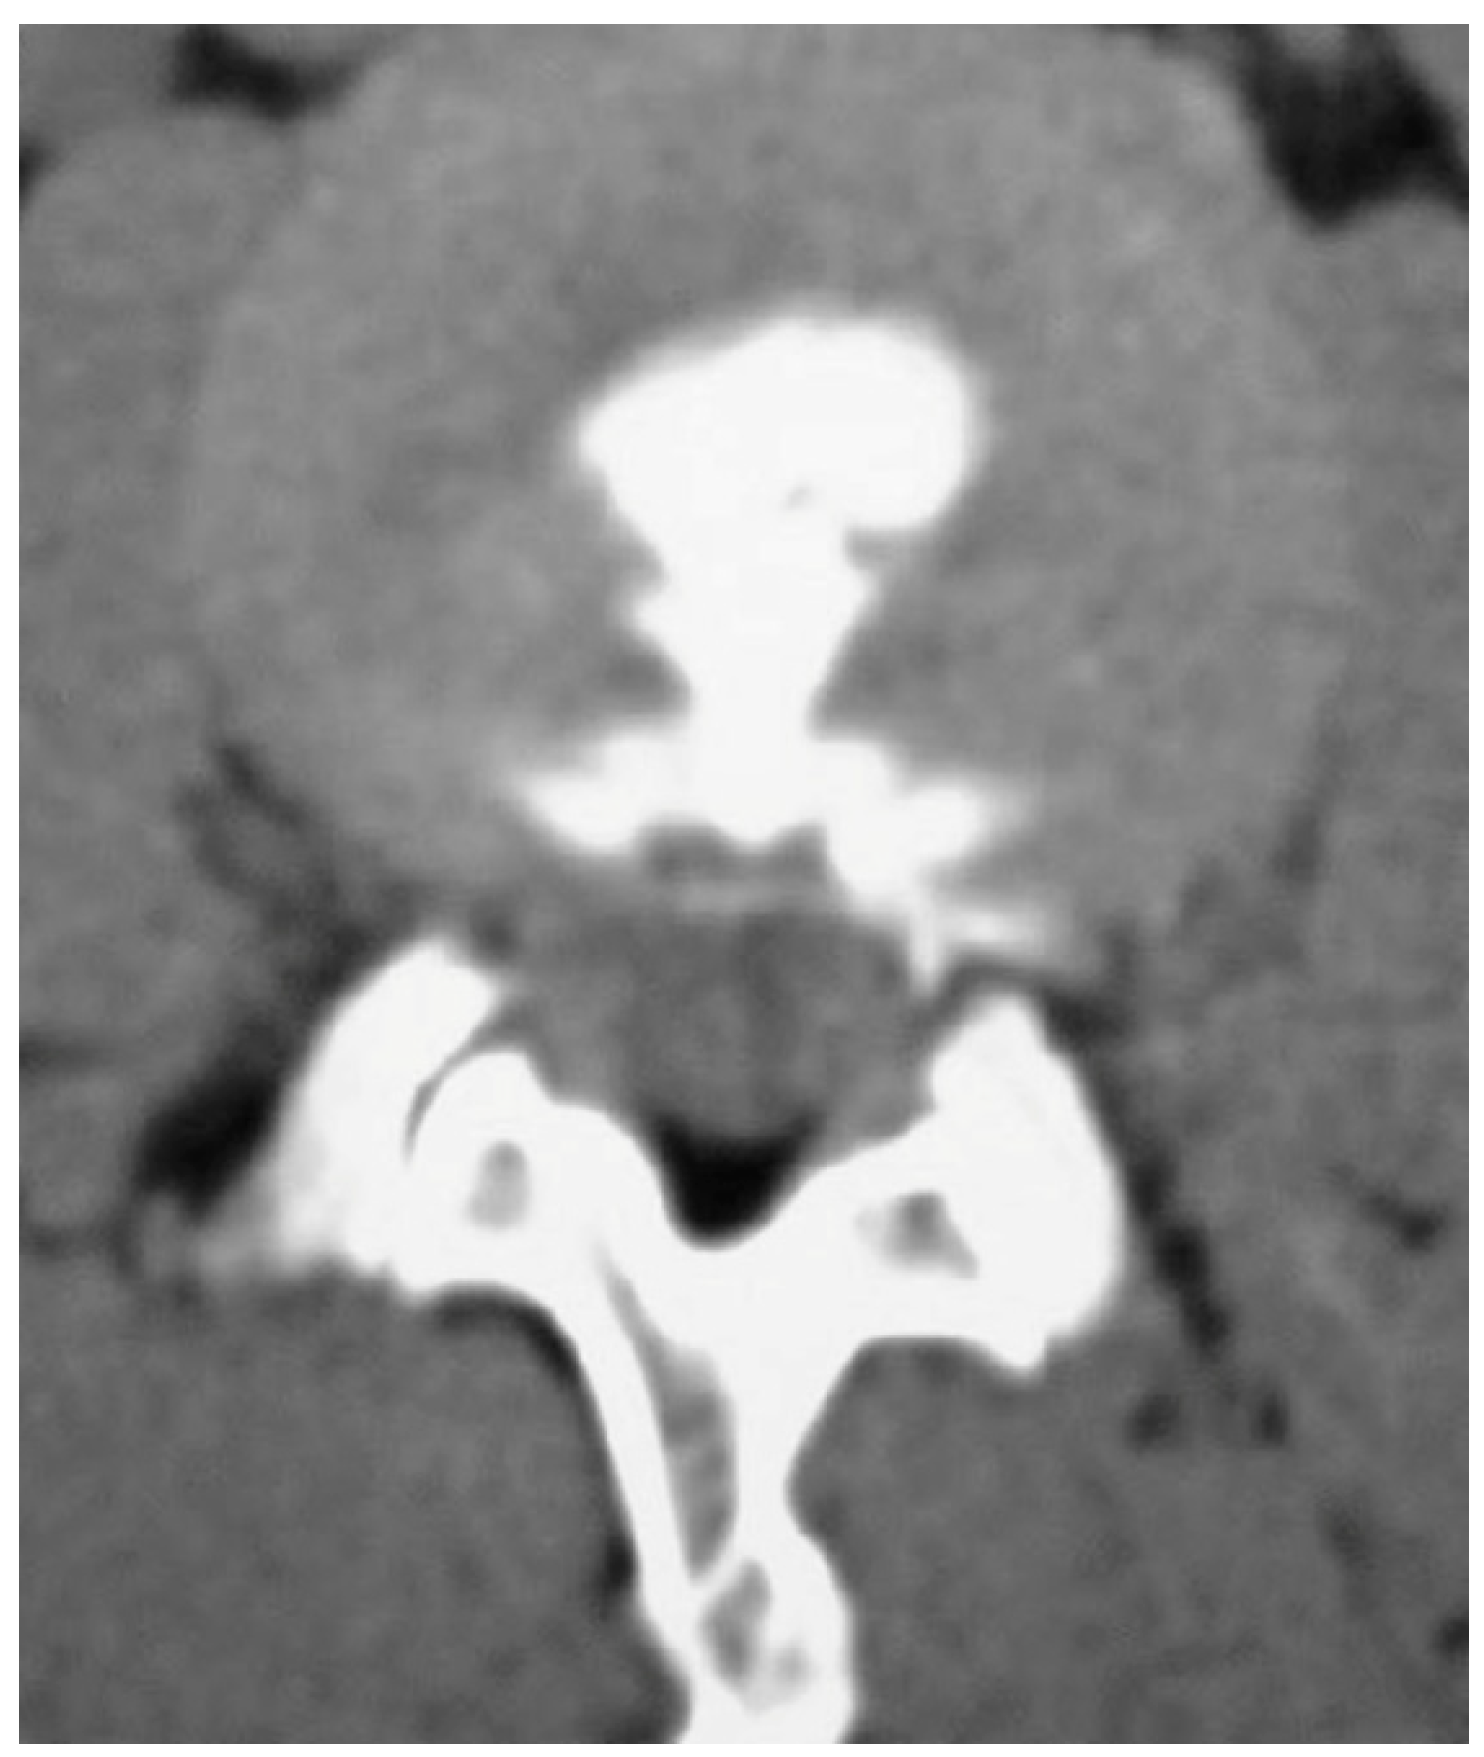

- Park, S.H.; Ji, G.Y.; Cho, P.G.; Shin, D.A.; Yoon, Y.S.; Kim, K.N.; Oh, C.H. Clinical Significance of Epidurography Contrast Patterns after Adhesiolysis during Lumbar Percutaneous Epidural Neuroplasty. Pain. Res. Manag. 2018, 2018, 6268045. [Google Scholar] [CrossRef] [PubMed]